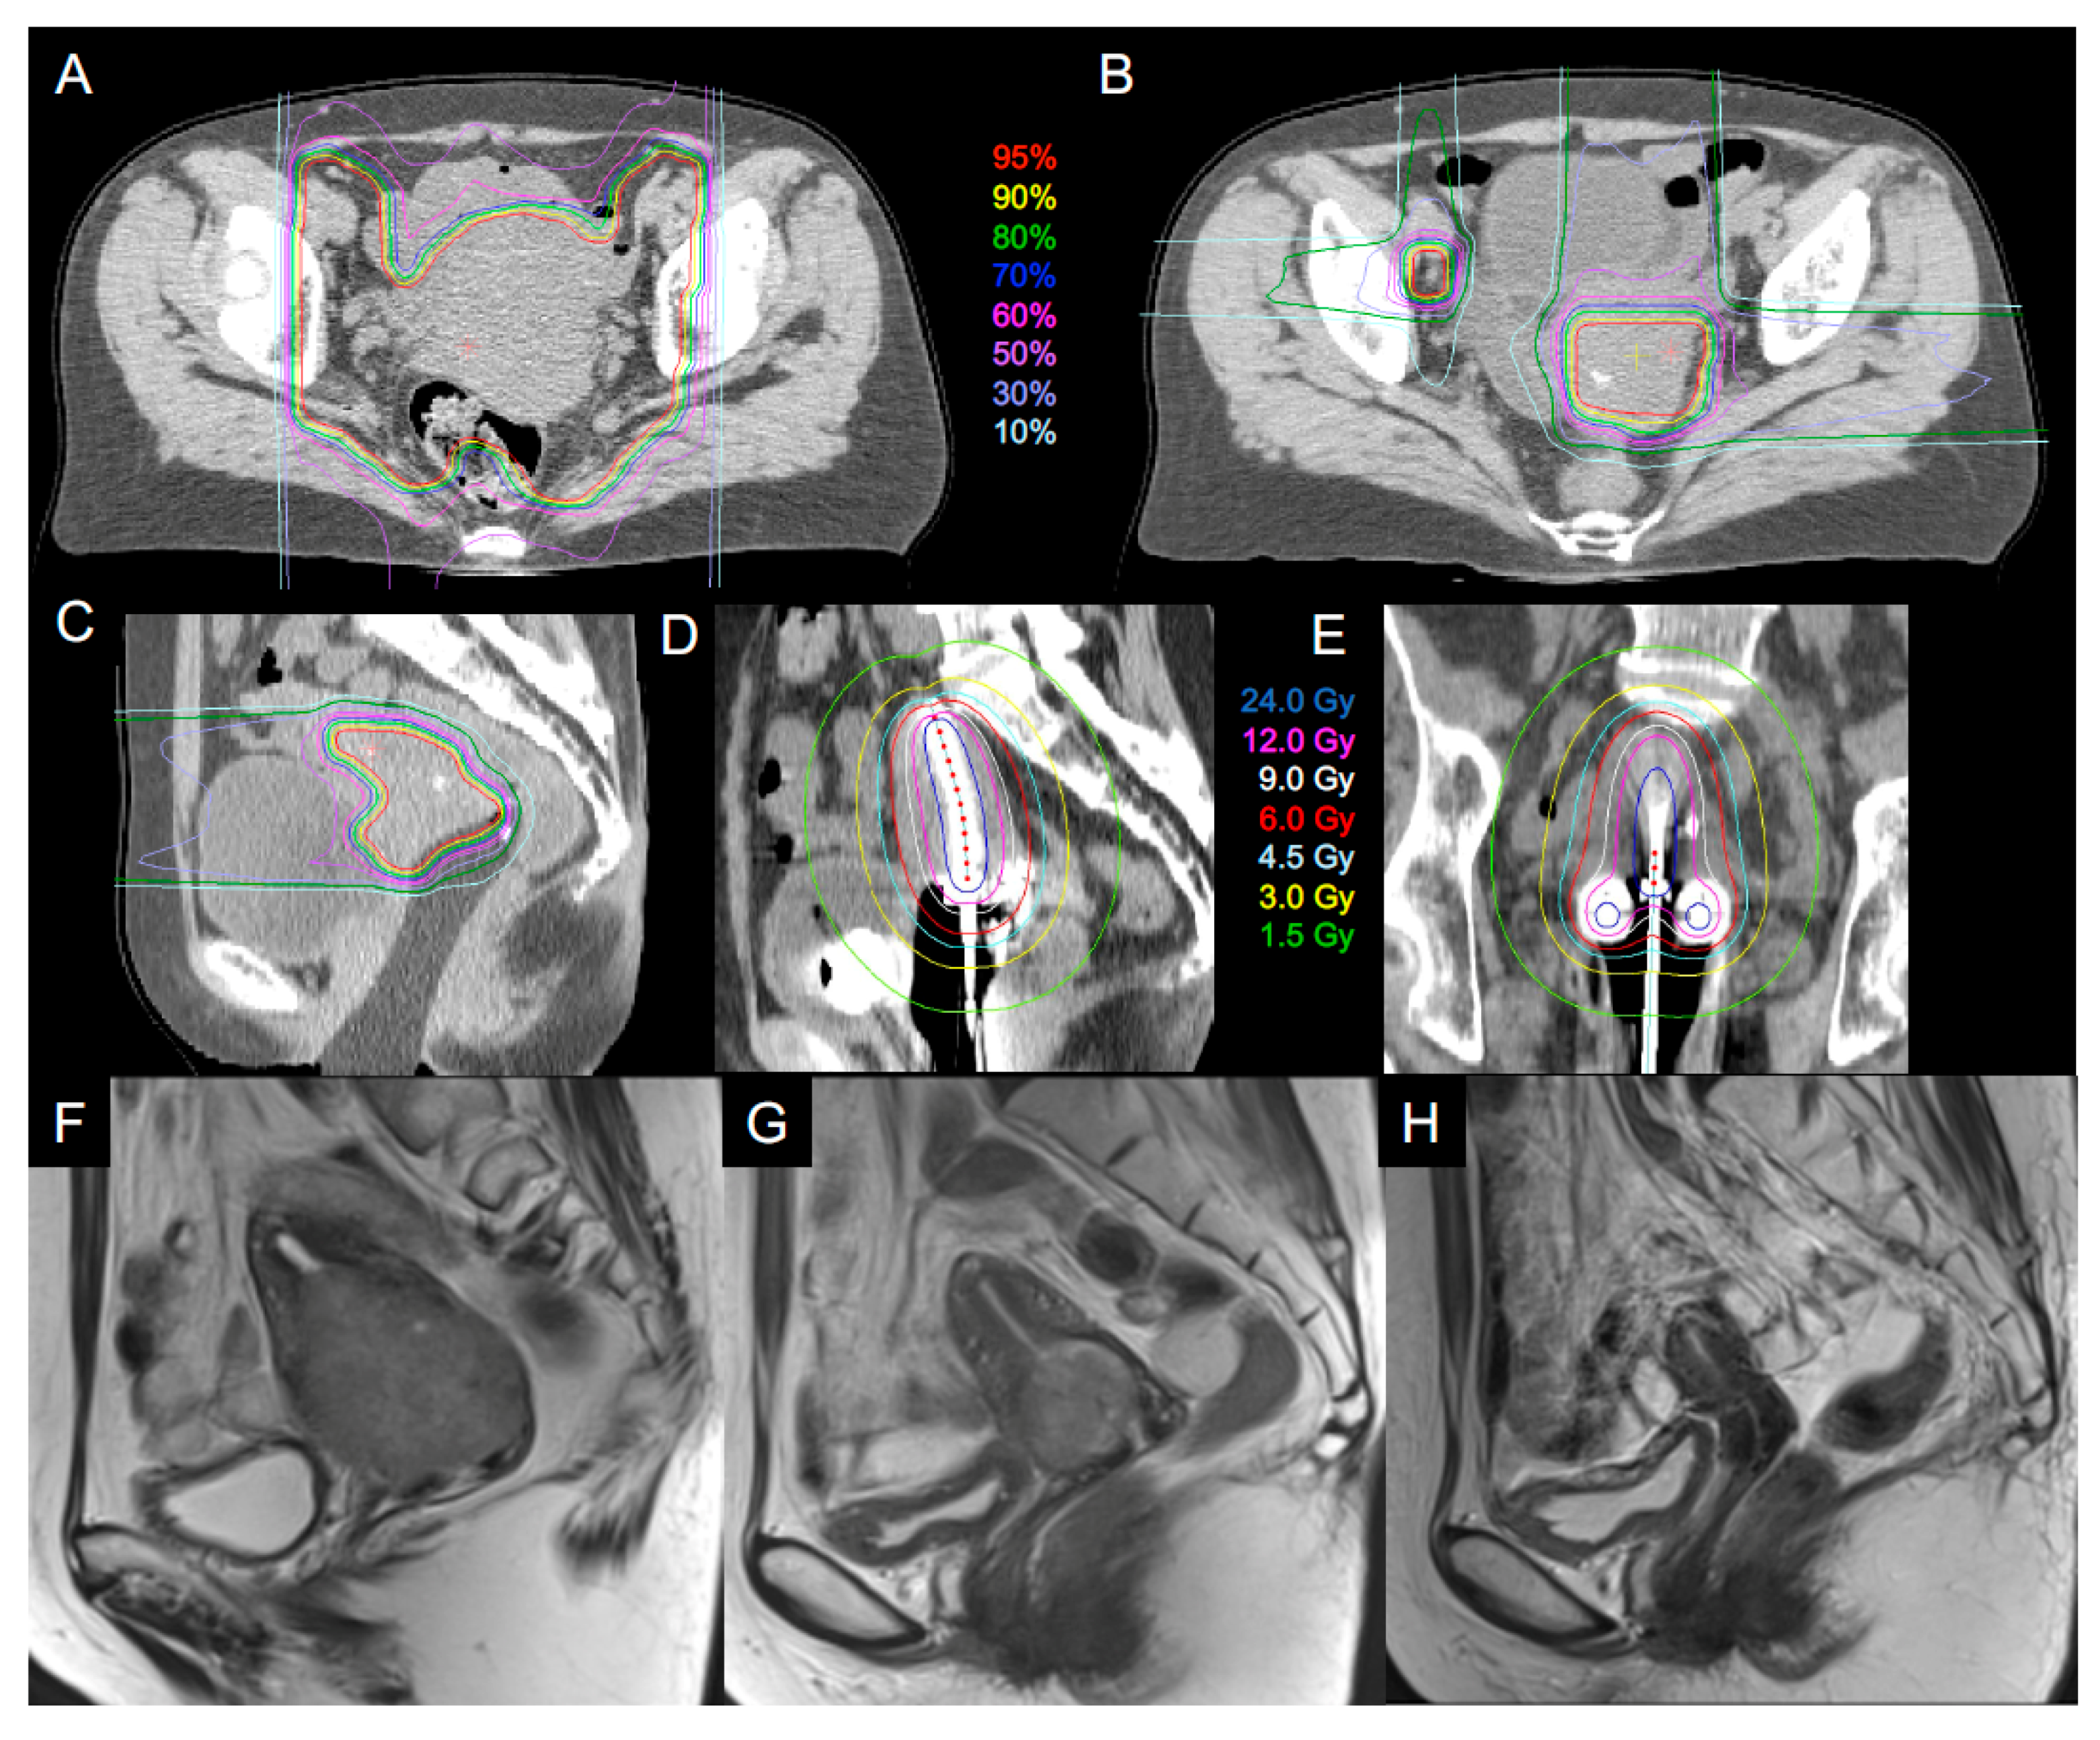

2.2. Carbon Ion Radiotherapy

2.3. Image-Guided Brachytherapy